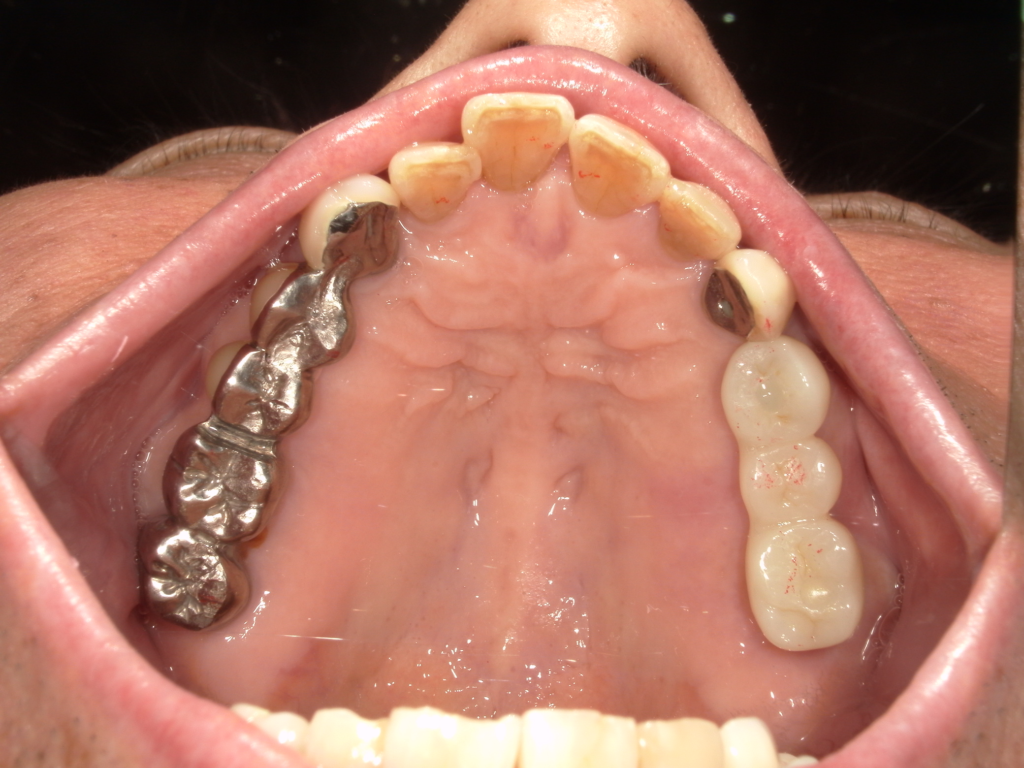

Y様インプラント実例 #44

左の上下の奥歯をインプラントで治療しています。

左下の奥歯は歯を抜くのと同時にインプラントの埋め込みを行っています。

被せものは上下、セラミックスで作っています。

治療前

治療後